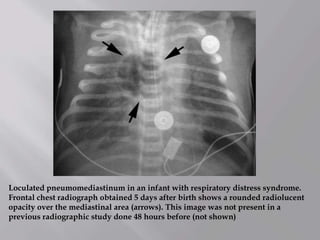

Loculated pneumomediastinum in an infant with respiratory distress syndrome.

Frontal chest radiograph obtained 5 days after birth shows a rounded radiolucent

opacity over the mediastinal area (arrows). This image was not present in a

previous radiographic study done 48 hours before (not shown)